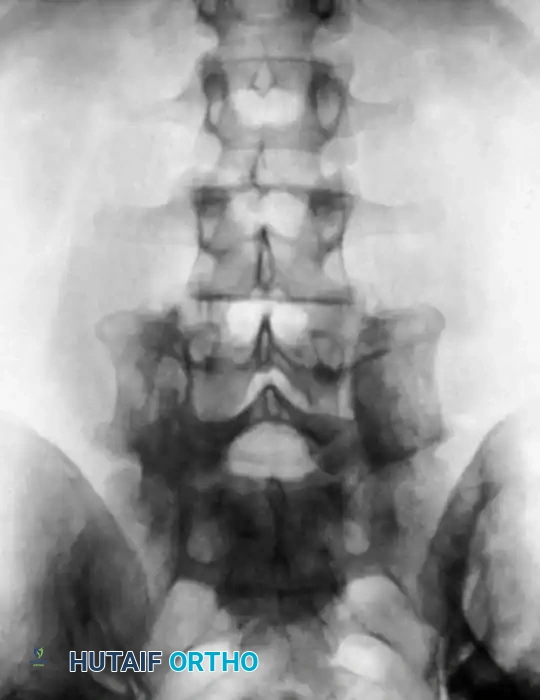

Accurate visual identification of a specific vertebral level is notoriously difficult in the dorsal and lumbar spine, except when the sacrum can be definitively exposed and identified. Despite anatomical peculiarities of spinous processes, laminae, and articular facets, relying solely on visual landmarks is fraught with error.

We strongly recommend a standardized method consisting of the radiographic identification of a radiopaque marker clamped securely to a spinous process within the operative field. The closer to the base of the spinous process the marker is inserted, the more accurate the identification. Cross-table lateral radiographs or anteroposterior (AP) fluoroscopic images taken on the operating table must be compared meticulously with high-quality preoperative radiographs.